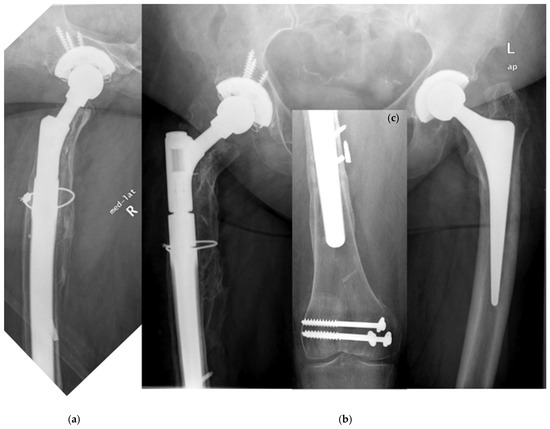

| Patient, Age at Surgery (ys.), Gender | Indication # | Bone Defect Paprosky et al. | Approach § | BMI (kg/m2) | Diabetes (y/n) | PPF Postop. (ys.) | Vancouver Classifi-cation | Conservative (C) vs. Operative Therapy (O) | Stem/Recon-Struction Length/Diameter (mm) * |

|---|---|---|---|---|---|---|---|---|---|

| 77, f. | TSR | 4 | TG | 20.8 | y | 4.2 | C | O (ORIF by Plate) | 290/14 |

| 68, f. | AL | 2B | TG | 22.5 | n | 0.8 | C | O (ORIF by Plate, Liss ©) | 250/18 |

| 73 +, f. | AL | 3B | TG | 34.4 | n | 8.6 | C | O (MIS by Plate, VA ©) | 290/21 |

| 75, f. | AL | 2B | TG | 25.9 | n | 9.8 | C | O (ORIF by Plate, VA ©) | 250/19 |

| 76, f. | AL | 2A | TG | 31.8 | n | 0.1 | B1 | O (ORIF by Plate, Liss ©) | 240/22 |